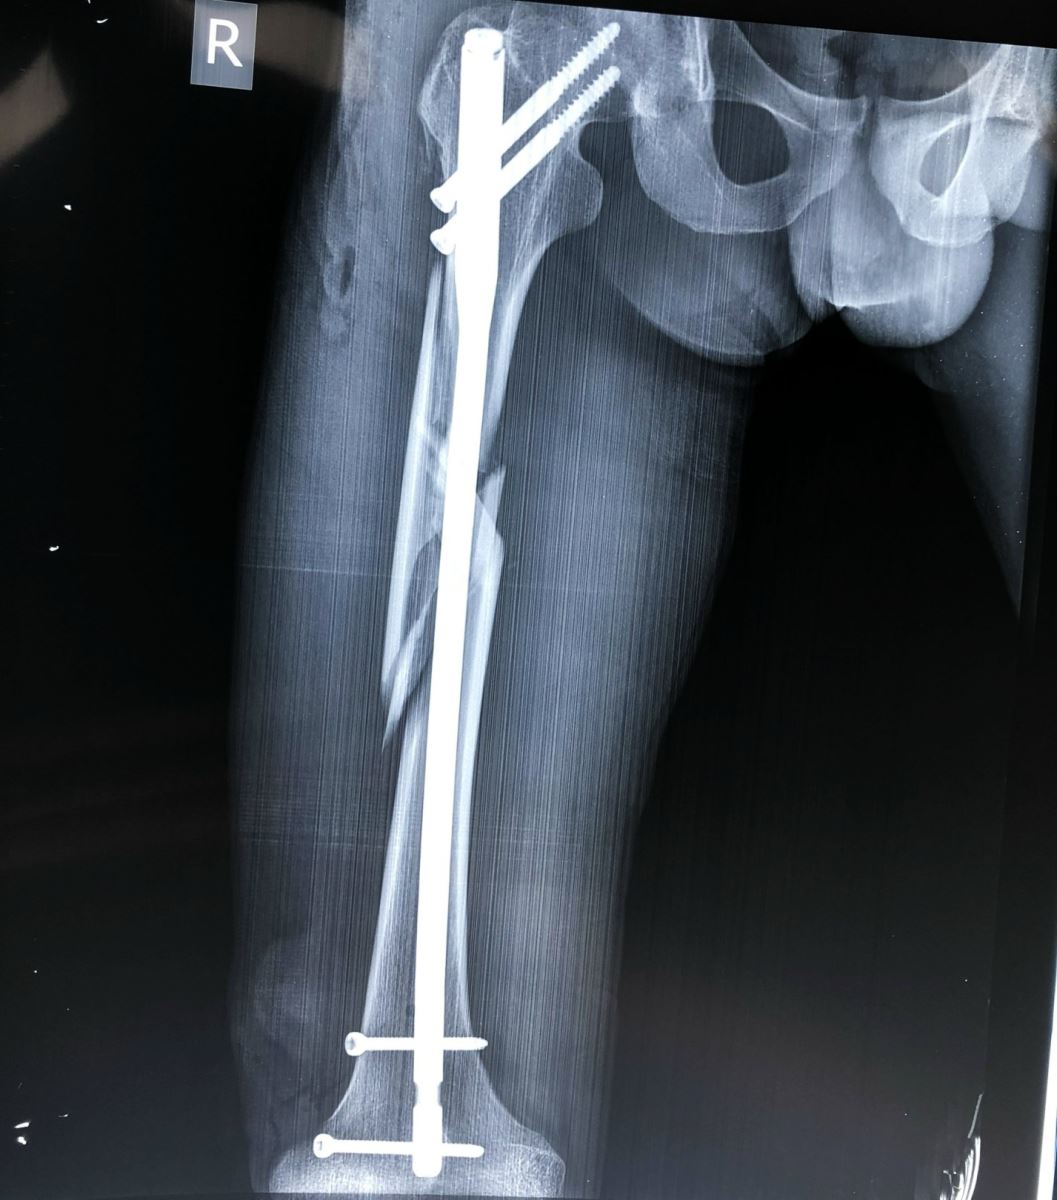

Đóng đinh nội tủy:

Áp dụng cho các trường hợp gãy thân xương đùi, tốt nhất đoạn 2/4 giữa, áp dụng trong tất cả các trường hợp gãy ngang, chéo, nhiều mảnh, gãy 2 ổ. Đóng đinh nội tủy được xem là phương pháp tốt nhất hiện nay. Nhờ màn tăng sáng, người ta đóng đinh không mở ổ gãy và có khoan rộng ống tủy. Để chống xoay của đoạn gãy xa người ta tăng cường chốt ngang qua xương. Trong trường hợp đường gãy thấp ở đoạn 1/3 giữa và dưới, có thể tiến hành đóng đinh nội tủy có chốt ngang ngược dòng từ đầu dưới xương đùi.